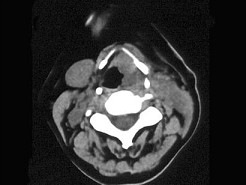

男,67岁,口咽部异物感约8个月,伴口咽部疼痛,患者无明显发热。如图所示最可能的

[单选题,A1型题] 男,67岁,口咽部异物感约8个月,伴口咽部疼痛,患者无明显发热。如图所示最可能的诊断为()A . 扁桃体结核伴淋巴结转移B . 扁桃体脓肿伴淋巴结转移C . 扁桃体癌伴淋巴结转移D . 扁桃体淋巴瘤E . 下咽癌伴淋巴结转移

男,67岁,口咽部异物感约8个月,伴口咽部疼痛,患者无明显发热.如图所示最可能的

[单选题]男,67岁,口咽部异物感约8个月,伴口咽部疼痛,患者无明显发热.如图所示最可能的诊断为()A .扁桃体结核伴淋巴结转移B .扁桃体脓肿伴淋巴结转移C .扁桃体癌伴淋巴结转移D .扁桃体淋巴瘤E .下咽癌伴淋巴结转移